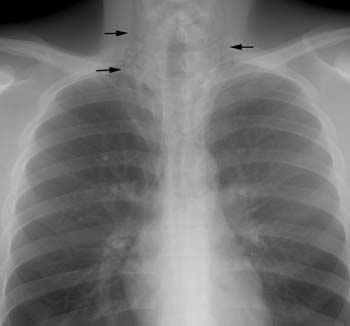

Scott WilliamsEndocrineEndocrine > Thyroid > I-131 for cancerApril 2, 2002PETPET > PET tumor imaging > Esophageal CancerApril 2, 2002Central Nervous SystemCNS > Seizure imagingApril 2, 2002CardiacCardiac > Valve > MRApril 2, 2002Tumor ImagingProstascint (111In-Capromab Pendetide) (CYT-356)April 2, 2002TumorTumor > Benign > AVMApril 2, 2002Miscellaneous PulmonaryMisc > Mediastinum > Images > Case1April 2, 2002PETPET CNS Imaging:April 2, 2002PETPET > PET tumor imaging > Head and Neck TumorsApril 2, 2002Vascular AbnormalitiesVascular > HemangiomatosisApril 2, 2002Previous PagePage 88 of 265Next PageTop StoriesCT5-year CTC screening interval is appropriate for colorectal cancerThe study's findings add to an ongoing conversation about the use of CTC for colorectal cancer screening.MRIASTRO: Daily MRgRT recontouring improves prostate treatment outcomesRadiation Oncology/TherapyASTRO: Radiation therapy comparable to surgery for early-stage lung cancerCTCT use in the ED has more than doubled over a decadeSponsor ContentDigital Innovations Shaping the Future of Radiology